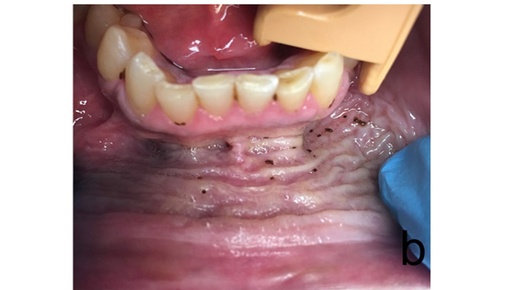

04-15 Табачные изделия, употребляемые через слизистую оболочку полости рта